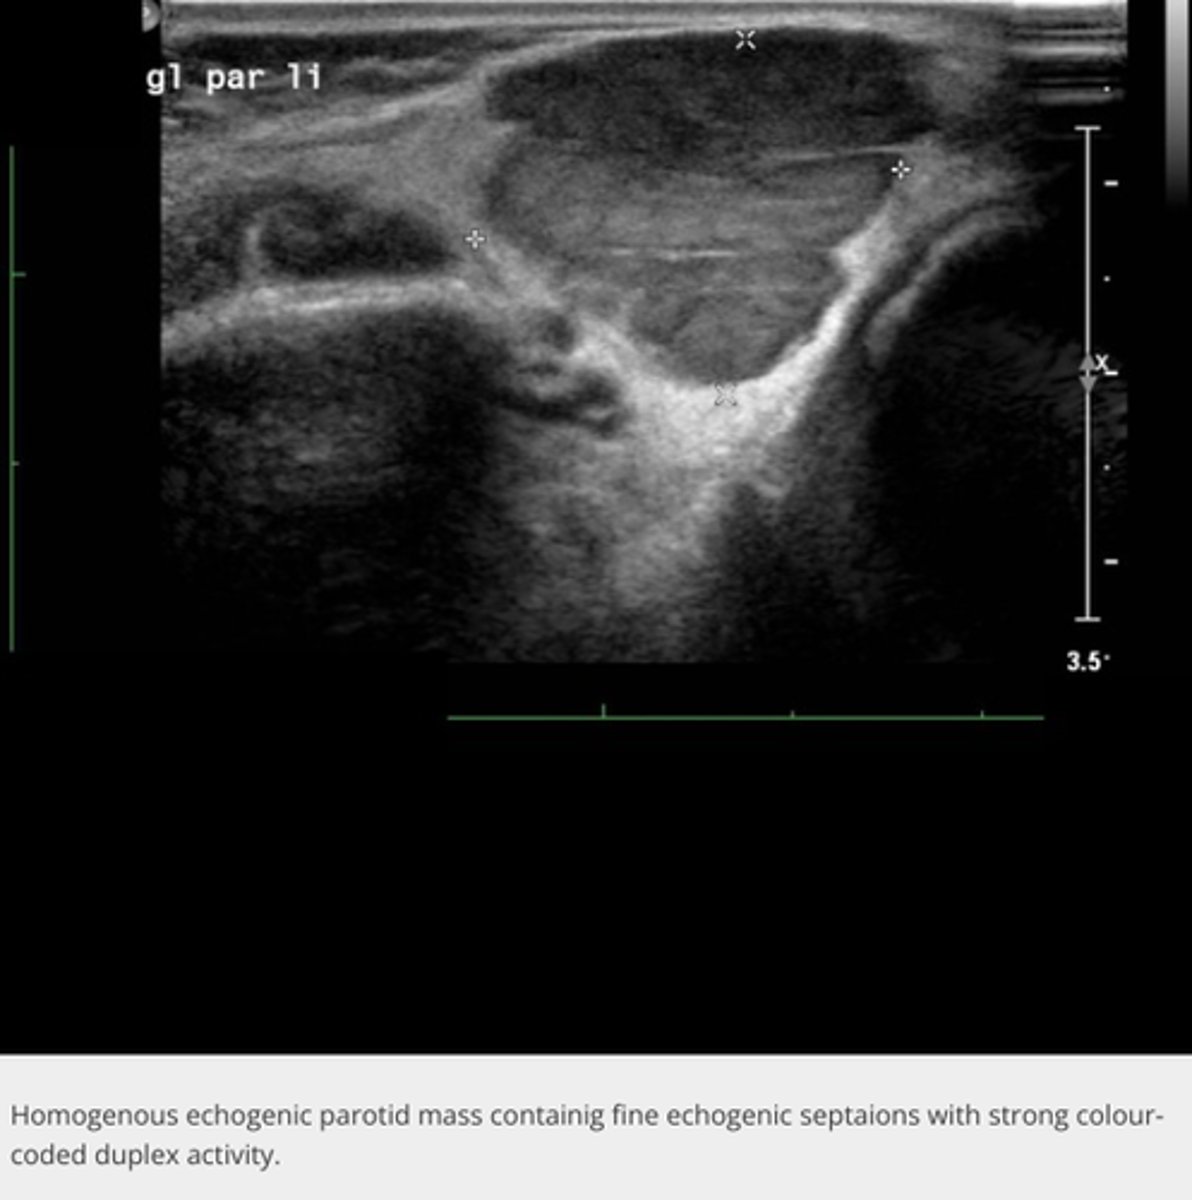

Salivary Glands:

-_____ glands divided into lobules with a hilum where branching blood vessels, ducts and nerves are present

Parotid gland

-_____ of the salivary glands

-Shaped like an _____

-Contains _____ duct (excretory duct)

-Only salivary gland that has intraparenchymal _____

-Largest of the salivary glands

-Shaped like an inverted pyramid

-Contains Stenson's duct (excretory duct)

-Only salivary gland that has intraparenchymal lymph nodes